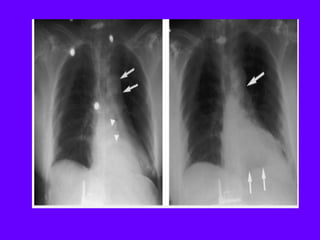

“septal pattern” characterised by

thickened smoothly interlobular

septae in the right parahilar area.

Right pleural effusion is also seen